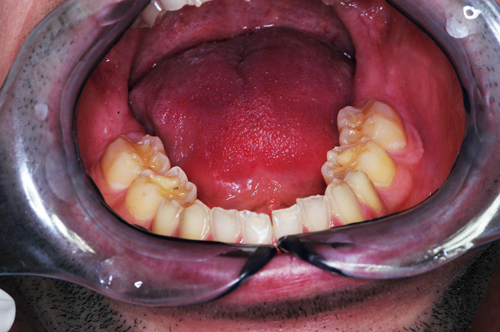

REHABILITACION ORAL MEDIANTE CORONAS DE PORCELANA DE ALTA DENSIDAD Protocolo D.A.T.O. CASO CLINICO: Paciente 24 años, bruxómano, atresia maxilar, referido por ortodoncista para realizar rehabilitación oclusal . Se observa a la inspección la presencia de una hipoplasia adamantina en todos los dientes anteriores, carencia de Guía Anterior , evidentes signos de Facetas Parafuncionales de Desgaste en los posteriores, y una marcada convergencia de los ejes dentarios ápico oclusal, tanto en el maxilar superior como en el inferior, siendo el superior el mas difícil de resolver dado que la inclinación de la Curva de Wilson es inversa a lo que presenta el enfermo. Radiograficamente sin patologías presentes. No presenta movilidades dentarias ni síntomas articulares en las ATM. Debido a la excesiva contractura de su musculatura, se realiza la relajación obviando el uso corriente de las Laminillas de Long, reemplazando el método por un Jig de Lucia el que se deja en boca desde la noche anterior a la cita, advirtiendo al paciente que no debe quitarlo en ningún momento , ya que de hacerlo se repetirían los engramas musculares anómalos que el enfermo presenta. En esas condiciones se toman registros intermaxilares mediante silicona de registros, y se registra el maxilar superior respecto del plano de Frankfort mediante arco facial estático. Se llevan a cabo los encerados correspondientes y se construye en base a ellos el primer juego de provisionales, los que no son cementados debido al perfecto anclaje que presenta. Transcurridos seis meses del uso de provisionales , durante los cuales se ha observado la Oclusión en Relación Céntrica (ORC) inalterable, la ausencia de desgastes patológicos (en las provisorias) y la ausencia de síntomas articulares y musculares, deducimos que el paciente se mantiene en una orto función adecuada, por lo cual comenzamos su rehabilitación definitiva construyendo su Guía Anterior ( determinante primario de la oclusión) en porcelana sobre porcelana de alta densidad.. Observamos los espacios correspondientes en los sectores posteriores y las Disclusiones de los mismos. Los tallados ha sido realizados mediante el concepto de Tallados Gnatológicos, recreados por el Prof. Alvarez Cantoni bajo la denominación de “Preparaciones Racionales”( PREPARACIONES RACIONALES EN PRÓTESIS PARCIAL FIJA. Ed. Hacheace) probando finalmente el trabajo luego de varios días de cementado provisional, y observando la adaptación periférica del borde cavo superficial , su aspecto estético y el importante factor disclusivo : CURVA DE WILSON. y verificando la eficacia lograda mediante una Oclusión Mutuamente Compartida, en la observación de una Disclusión derecha en el Lado de Trabajo y no Trabajo de una disclusión izquierda como así también en la disclusión propulsiva Utilizamos papel de articular de ocho(8) micras para verificar la eficacia de las disclusiones. y de los puntos interoclusales de contacto ANTES DESPUES

Luego de un par de entrevistas, se le informa acerca de la hipofunción masticatoria evidente, producto de la destrucción no solo de las piezas anteriores, sino también de la paulatina generación de Facetas Parafuncionales de Desgaste que determinan una eficacia masticatoria deficiente.

Facetas estas donde puede observarse el típico fenómeno de “DESGASTE EN OLLA”, constituido por el facetamiento doblemente profundo de las Cúspides Estampadoras respecto de las Cúspides de Corte.